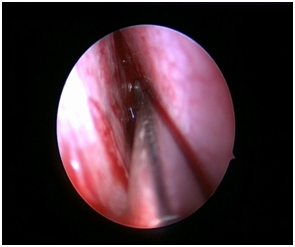

Nasal Endoscopy is done to assess the septal deviation and spurs (Figure 1) ( Figure 2). Septal infiltration is carried out with a solution of 2% Xylocaine with 1: 100,000 adrenaline in the sub-mucosal plane. It is given with a single prick at the inferior most part of the nasal septum at the junction of the septum with the floor of the nasal cavity anterior to the mucocutaneous junction. The infiltration is given at the same point on both the sides (Figure 3). The incision is always given on the deviated side. It is given anterior to the mucocutaneous junction because the skin present at that place is thick and chance of a tear of the flap is less (Figure 4). The mucoperichondrial flap is raised on the deviated side with a Freer’s elevator strictly under vision. The flap is not to be raised beyond the deviated part because the part of the septum posterior to the deviation is not under direct vision (Figure 5) (Figure 6). The caudal end of the septum is then palpated and an incision is given on the cartilage 1cm behind the columella. This 1cm of the cartilage is saved to prevent post operative tip deformities (Figure 7). The cartilage is sliced and the opposite side is entered, the mucoperichondrial flap of the opposite side is then elevated with a Freer’s elevator. A cut is given in the septal cartilage as high as possible. A septal window is created and a Ballenger’s swivel knife is taken and lodged in the place where the cartilage was cut. Creation of a septal window thus increases the area of exposure (Figure 8) (Figure 9). The flap on the non-deviated side is elevated till the bony-cartilaginous junction.

Figure 5 Elevation of flap on left side.

Figure 6 Elevation of the non-deviated side.